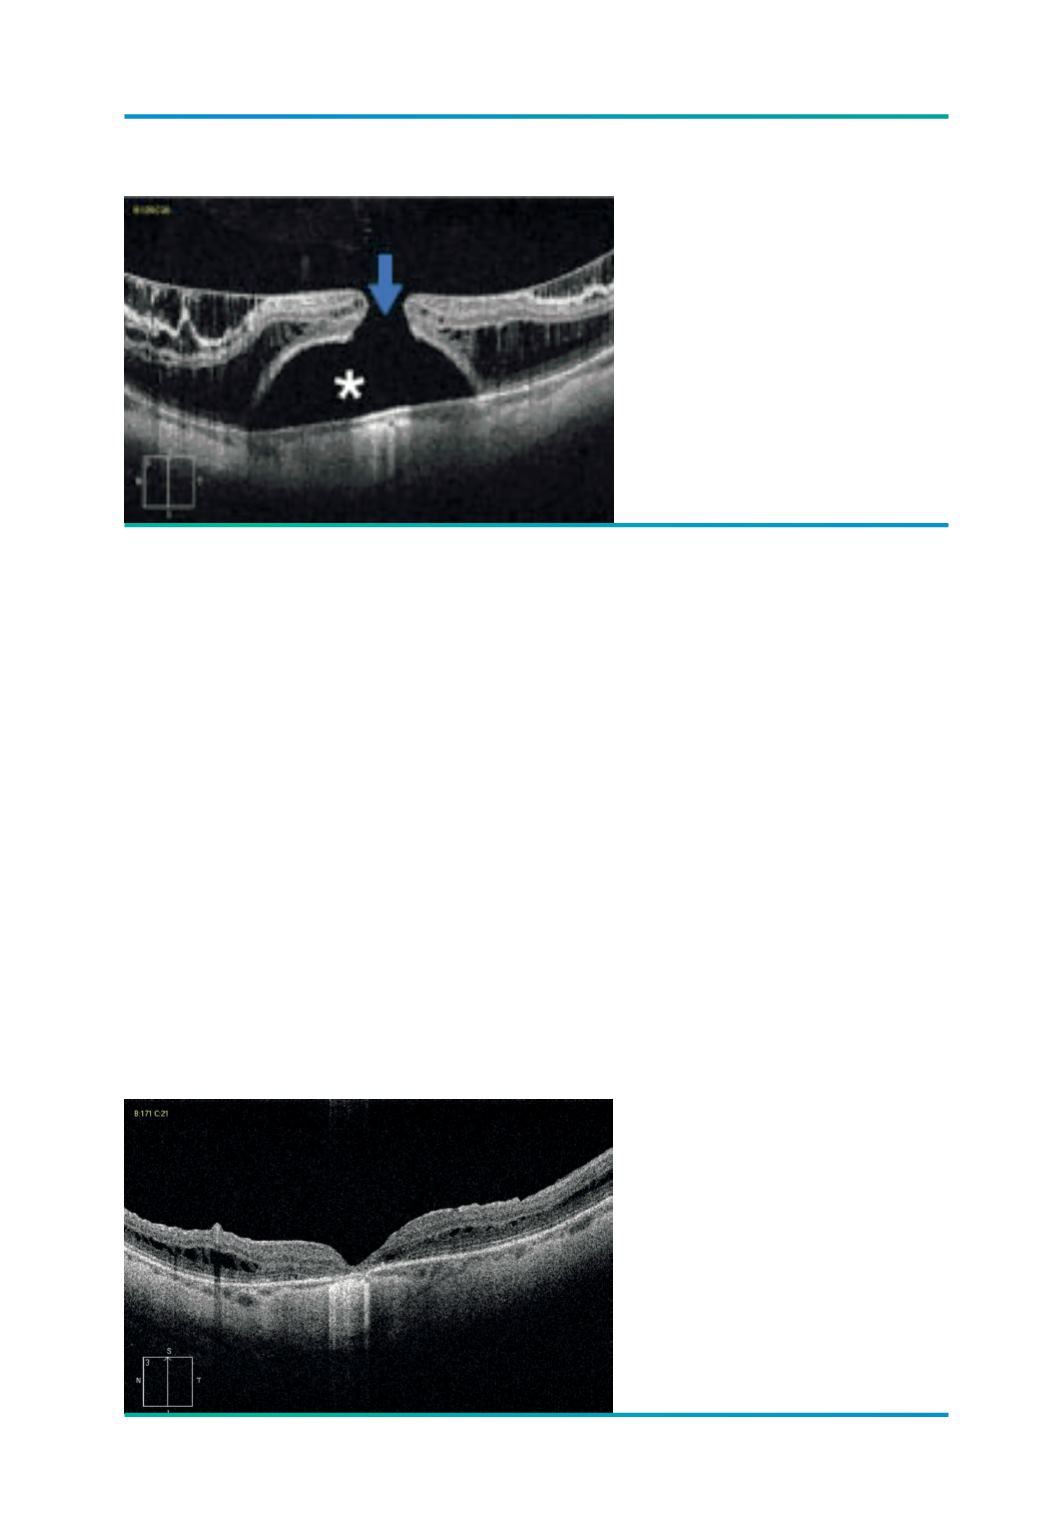

Figura 7.

Foveosquisis, descolamento foveal

(*) e BMM (

→

); VOD - 1/10 cc, com

metamorfopsias.